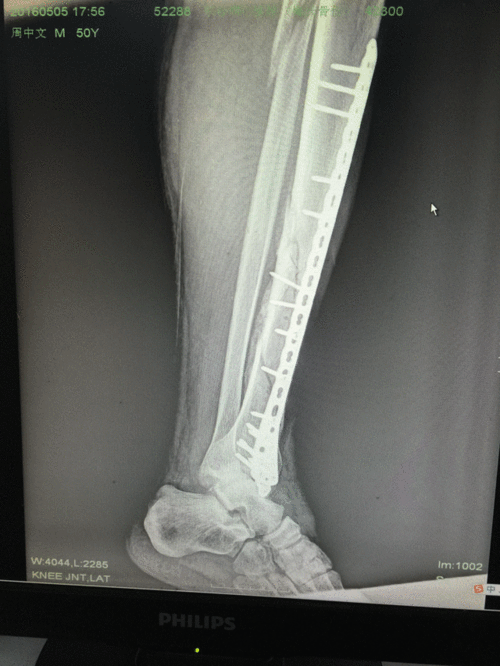

胫腓骨粉碎性骨折,小切口植入加长钢板,告别传统大切口

粉碎性骨折钢板

粉碎性骨折手术

粉碎性骨折上钢板图片